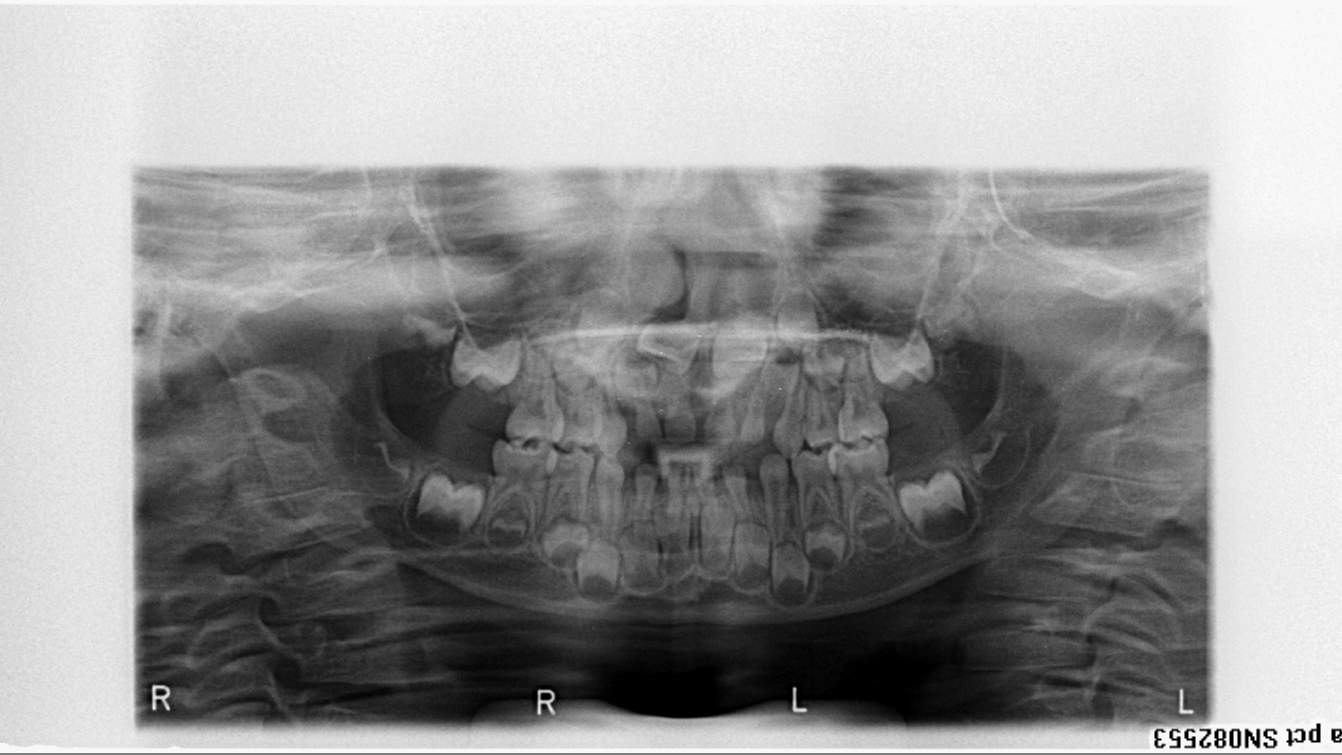

bilan début et en cours de traitement

bilan des radiographies début et en cours de traitement